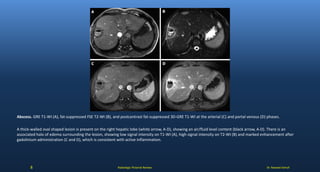

Abscess. GRE T1-WI (A), fat-suppressed FSE T2-WI (B), and postcontrast fat-suppressed 3D-GRE T1-WI at the arterial (C) and portal venous (D) phases.

A thick-walled oval shaped lesion is present on the right hepatic lobe (white arrow, A-D), showing an air/fluid level content (black arrow, A-D). There is an

associated halo of edema surrounding the lesion, showing low signal intensity on T1-WI (A), high signal intensity on T2-WI (B) and marked enhancement after

gadolinium administration (C and D), which is consistent with active inflammation.